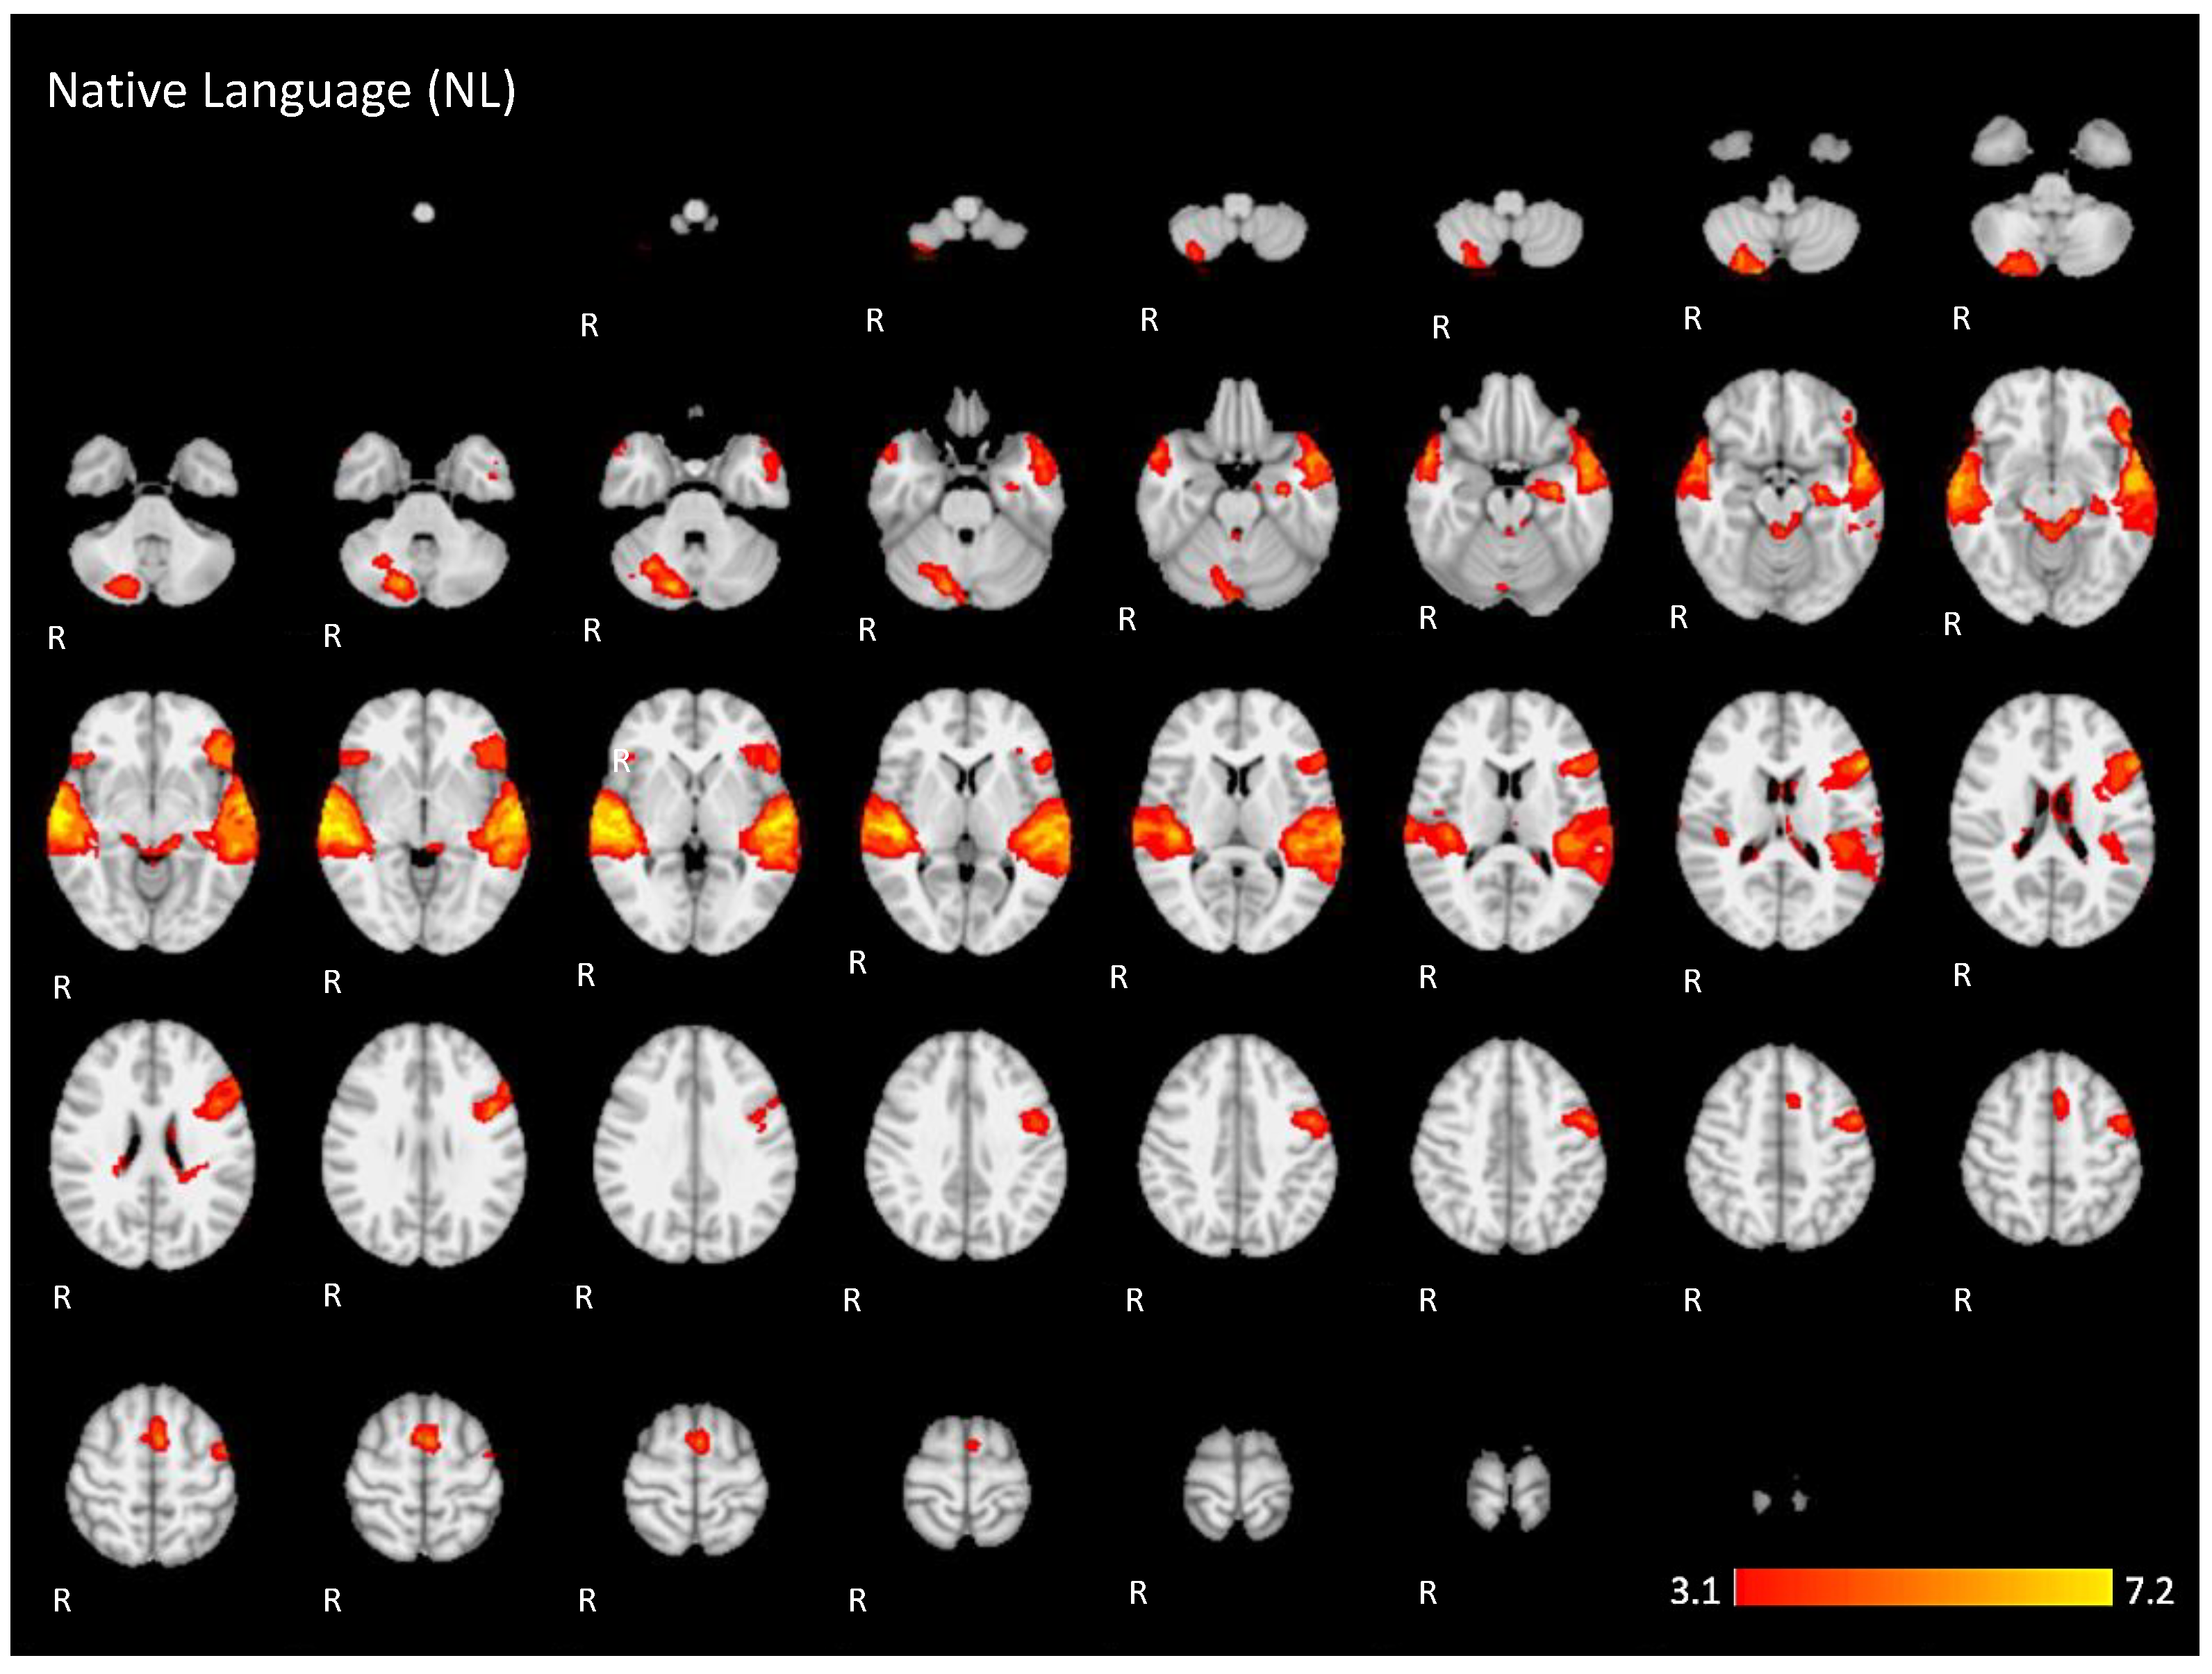

In the active condition NL (native language) compared to the baseline, significant BOLD signal activations were observed in regions considered as part of the ventral and dorsal language networks: the right inferior frontal gyrus pars triangularis, the bilateral superior temporal gyrus with extended activation into the middle temporal gyrus, and the inferior temporal gyrus in the left hemisphere. Furthermore, activation was found in areas described as part of the Multiple Demand network in the middle frontal gyrus, the paracingulate gyrus, and the precentral gyrus. Additional activation was found in the right posterior lobe of the cerebellum and the bilateral middle parahippocampal gyrus, with extension into the left hippocampus, as shown in Figure 5 (images of first line) and Figure A1 (Appendix A).

Figure 5.

Two-dimensional fMRI map of auditory attention task (n = 25). BOLD signal clusters (in red) are observed in the following brain regions: First row is condition 1 (native language—NL) versus baseline; second row is condition 2 (unknown language—UL) versus baseline; third row is the contrast “native language” > “unknown language”; fourth row is the contrast “unknown language” > “native language”. (Red–yellow scale indicates the z-score > 3.1; p < 0.05).

The brain activation maps are shown in Figure 5 using the main slices of the 2D fMRI maps for the active conditions NL and UL and for the contrasts NL > UL and UL > NL. The 2D fMRI maps of all brain slices for both active conditions (NL, UL) and for both contrasts (NL > UL and UL > NL) are in Appendix A (Figure A1, Figure A2, Figure A3 and Figure A4, respectively).

Figure A1.

Two-dimensional fMRI map of auditory attention task (n = 25) for the contrast native language condition higher than baseline. (Red–yellow scale indicates the z-score > 3.1; p < 0.05).